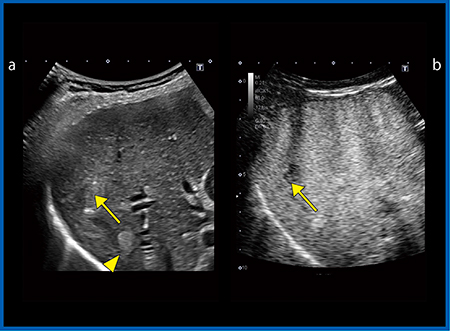

図4 aは,↑が肝細胞がん(HCC),▲が肝血管腫であるが,従来プローブでは深部臓器の造影を行っても十分な感度が得られず,特にpost vascular phaseで抜けているかどうかの判断が難しい。また,高エコーの腫瘍の観察ではゲインを上げて超音波の減衰をカバーするが,ノイズが増加し余計にわかりづらくなる。しかし,iDMS PVI-475BXでは,深部まで非常に均一で安定した感度が得られる(図4 b)。HCCでは造影剤が抜け始めているが肝血管腫では抜けておらず,Amplitude Modulation(AM)法でも造影剤の有無が確認でき,より確実な診断が可能となる。

図4 HCCと肝血管腫における従来プローブ(a)と

iDMS PVI-475BX(b)の比較